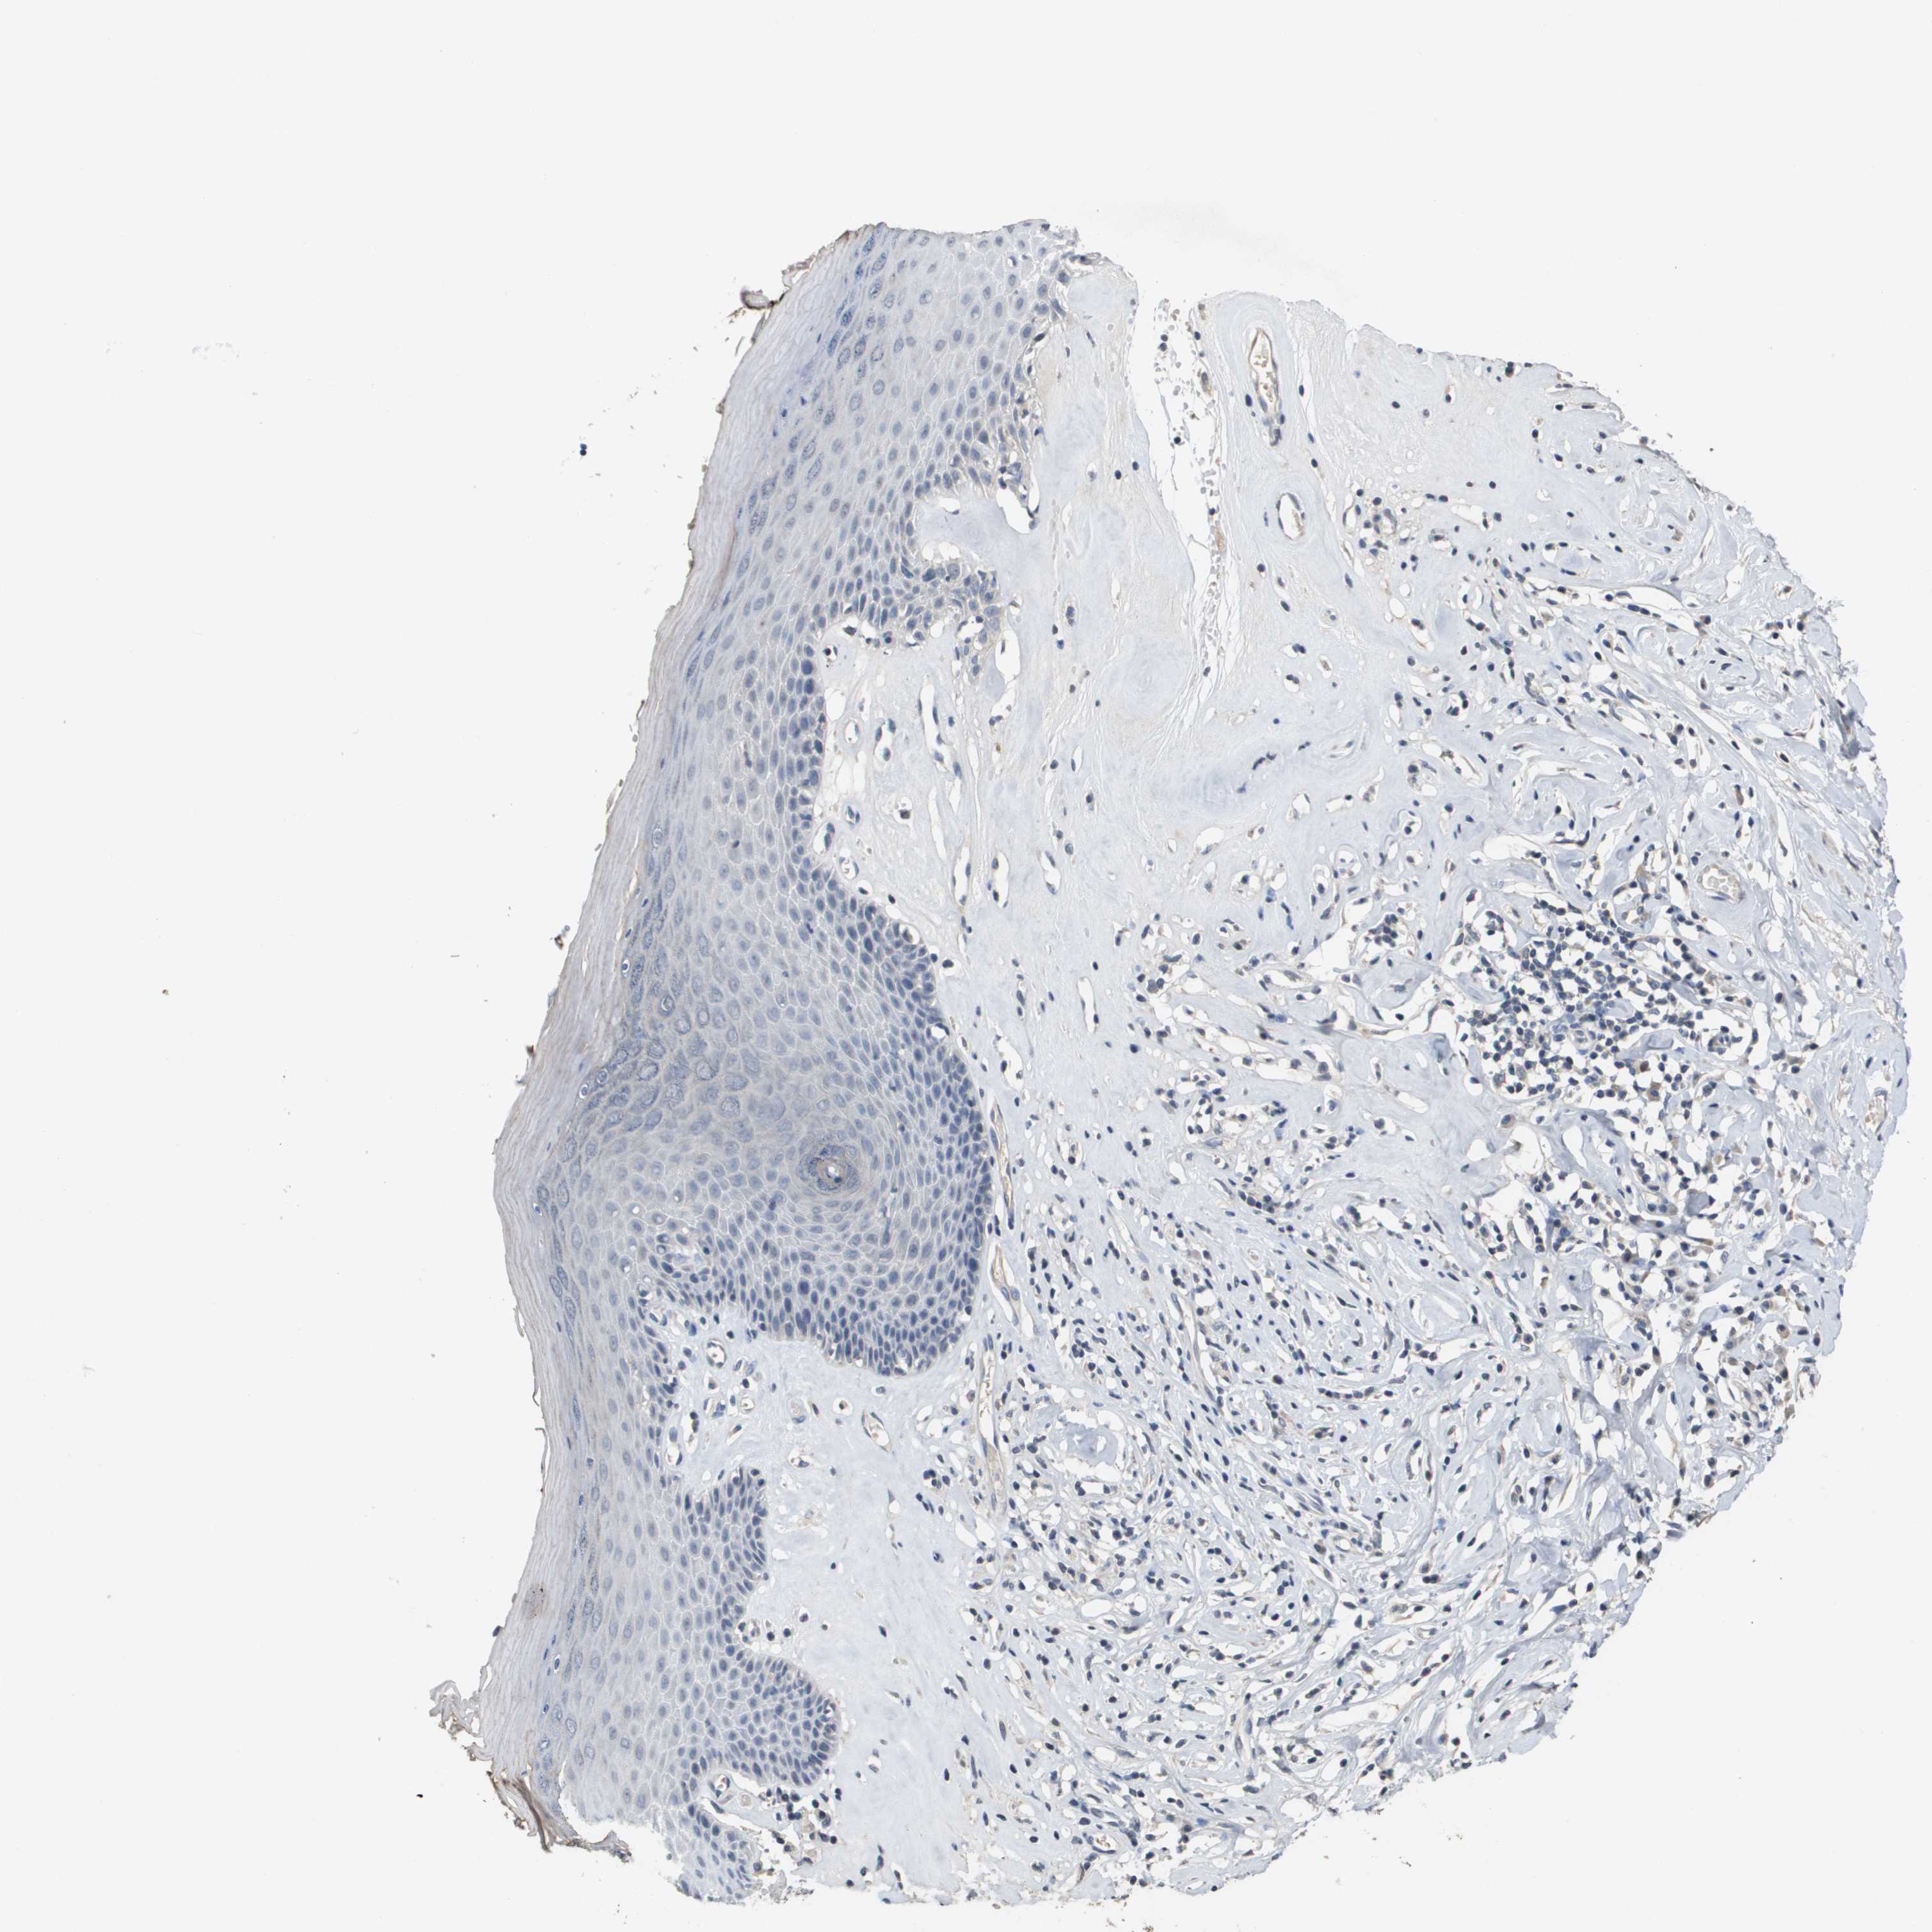

SKIN 1 - Antibody stainingi

Antibody staining in the annotated cell types in the current human tissue is reported as not detected, low, medium, or high, based on conventional immunohistochemistry profiling in selected tissues. This score is based on the combination of the staining intensity and fraction of stained cells.

Each image is clickable and will lead to virtual microscopy that enables deeper exploration of all samples and also displays staining intensity scores, fraction scores and subcellular localization as well as patient and tissue information for each sample.

Antibody HPA030955Antibody CAB018070

Langerhans Not detectedNot detected

Fibroblasts LowNot detected

Keratinocytes Not detectedNot detected

Melanocytes Not detectedNot detected